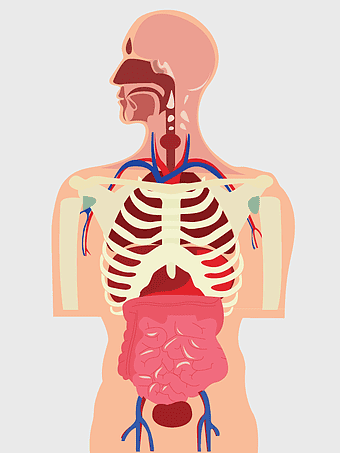

human anatomy diagram, digestive system illustration, human internal organs, Homo sapiens muscular system, anatomical art for education, systemic physiology chart, medical biology graphics -

768x1086px

human anatomy illustration, human organ system diagram, human body internal organs, human digestive system, anatomical chart, medical illustration, physiological diagram -

615x1600px

human body cartoon, human digestive system illustration, human anatomy diagram, human internal organs, medical illustration, skeletal system cartoon, human physiology art -

504x599px